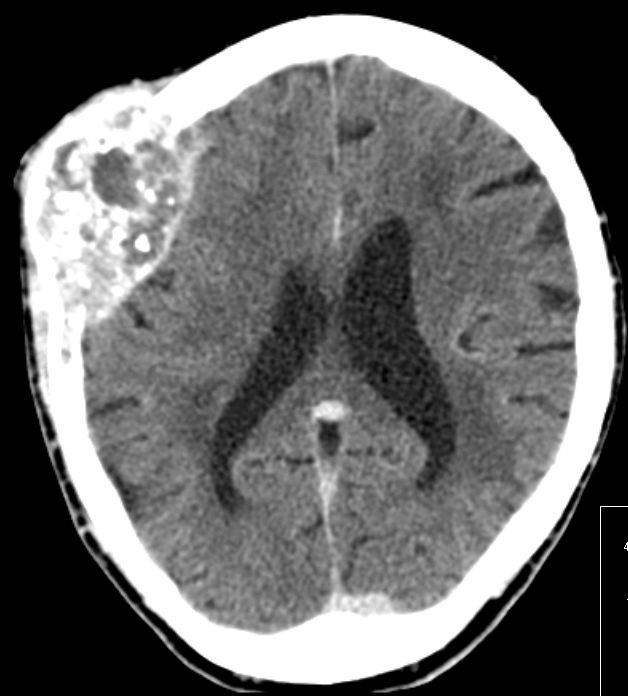

| Schädel | 86-jährige Frau mit primär ossär metastasiertem Adenokarzinom des linken Oberlappens.

Monate nach Diagnose klagte die Patientin über eine schmerzlose Schwellung des Kopfes rechts. Das Nativ-CT zeigt eine Metastase des Schädelknochens.![]() |

Nach KM-Gabe deutliche Kontraststeigerung.![]() |

Im Knochenfenster deutlich größere Zerstörung sichtbar.![]() |